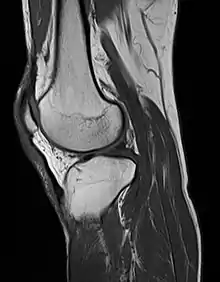

MRI uses strong magnetic fields to align atomic nuclei (usually hydrogen protons) within body tissues, then uses a radio signal to disturb the axis of rotation of these nuclei and observes the radio frequency signal generated as the nuclei return to their baseline states.[9] The radio signals are collected by small antennae, called coils, placed near the area of interest. An advantage of MRI is its ability to produce images in axial, coronal, sagittal and multiple oblique planes with equal ease. MRI scans give the best soft tissue contrast of all the imaging modalities. With advances in scanning speed and spatial resolution, and improvements in computer 3D algorithms and hardware, MRI has become an important tool in musculoskeletal radiology and neuroradiology.

One disadvantage is the patient has to hold still for long periods of time in a noisy, cramped space while the imaging is performed. Claustrophobia (fear of closed spaces) severe enough to terminate the MRI exam is reported in up to 5% of patients. Recent improvements in magnet design including stronger magnetic fields (3 teslas), shortening exam times, wider, shorter magnet bores and more open magnet designs, have brought some relief for claustrophobic patients. However, for magnets with equivalent field strengths, there is often a trade-off between image quality and open design. MRI has great benefit in imaging the brain, spine, and musculoskeletal system. The use of MRI is currently contraindicated for patients with pacemakers, cochlear implants, some indwelling medication pumps, certain types of cerebral aneurysm clips, metal fragments in the eyes and some metallic hardware due to the powerful magnetic fields and strong fluctuating radio signals to which the body is exposed. Areas of potential advancement include functional imaging, cardiovascular MRI, and MRI-guided therapy.